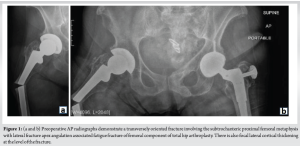

The index patient is an 88-year-old female with a body mass index (BMI) of 21.3 and a history of multiple comorbidities, including hyperlipidemia, hypertension, cerebrovascular accident, chronic kidney disease stage III, diabetes mellitus, and osteoporosis with bisphosphonate therapy. One year prior, she underwent an uncomplicated right total hip arthroplasty (THA) with a long cylindrical, fully porous-coated femoral stem. The prior THA was uncomplicated, and she had no prodromal symptoms. She presented following a ground-level fall, resulting in an APFF of the right femur. Radiographic findings revealed a transverse fracture through the subtrochanteric region of the femur, with breakage of the cylindrical femoral stem (Fig. 1a and b). Interestingly, the fracture also demonstrated lateral cortical thickening, a feature commonly associated with AFFs in patients on bisphosphonate therapy [3]. Although the fracture in this case met all five criteria, the ASBMR definition excludes periprosthetic fractures from the AFF definition [3]; therefore, this case demonstrates an APFF.